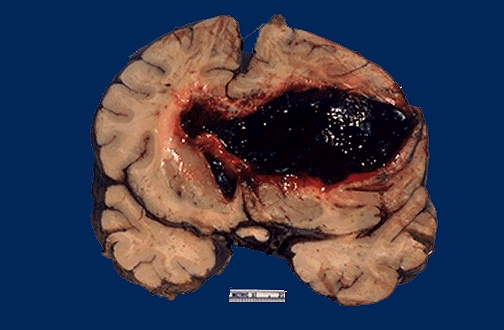

The large hemorrhage in this adult brain arose in the basal ganglia region of a patient with hypertension. This is one cause for a "stroke". [Image contributed by Jeannette J. Townsend, MD, University of Utah]